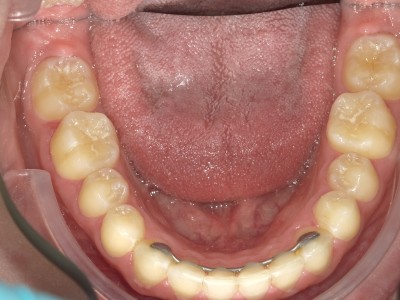

13-24 maand volledig vast onderkaak en bovenkaak + Transforce bovenkaak